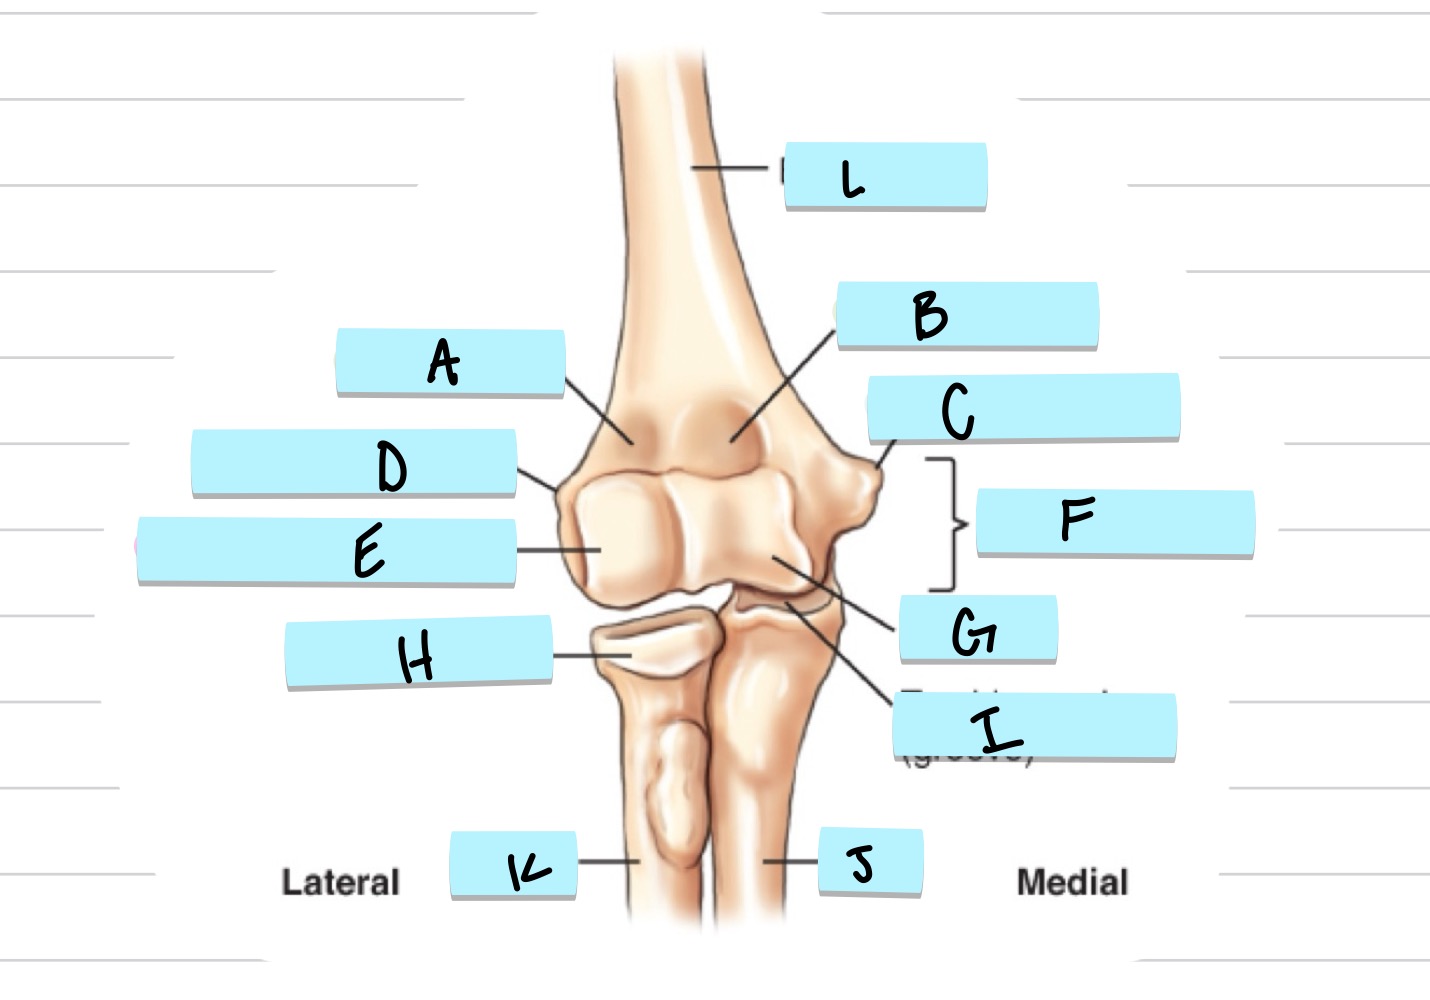

<p>What is A?</p>

What is A?

olecranon process

<p>what is B?</p>

what is B?

trochlear notch

<p>what is C?</p>

what is C?

coronoid process

<p>what is D?</p>

what is D?

radial notch

radial fossa

coronoid fossa